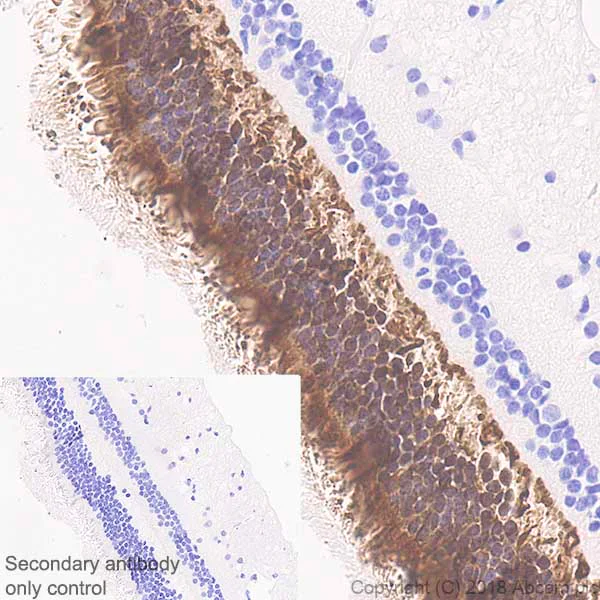

Immunohistochemistry (Formalin/PFA-fixed paraffin-embedded sections) - Anti-PHOS/PDC antibody [EPR21913] - BSA and Azide free (AB234531)

Immunohistochemical analysis of paraffin-embedded human retina tissue labeling PHOS/PDC with ab221138 at 1/2000 dilution, followed by Rabbit specific IHC polymer detection kit HRP/DAB (ab209101) ready to use. Positive staining on human retina, performed on a Leica Biosystems BOND® RX instrument (PMID : 11287646, PMID : 10617777, PMID : 15842737) is observed. Counterstained with hematoxylin.

Secondary antibody only control : Used PBS instead of primary antibody, secondary antibody is Rabbit specific IHC polymer detection kit HRP/DAB (ab209101) ready to use.

Antigen retrieval was performed using Bond™ Epitope Retrieval Solution 2 (pH 9.0).

This data was developed using the same antibody clone in a different buffer formulation containing PBS, BSA, glycerol, and sodium azide (ab221138).